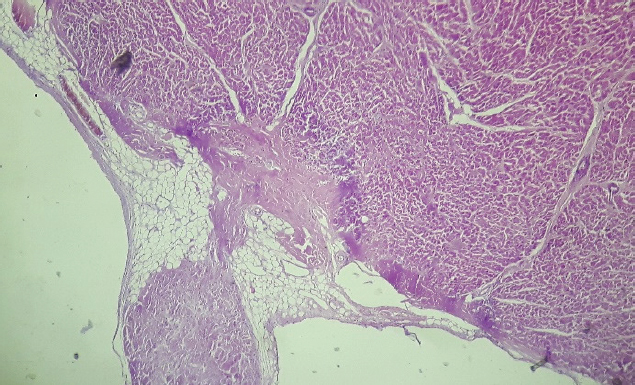

After 24 Holter monitoring, the patient died suddenly during physical activity. Permission for conducting necropsy was obtained from the animal owners. Postmortem examination showed marked cardiomegaly (heart weight bigger than 13 g/kg body weight). No lung edema, pleural effusion or ascites were observed. The heart was explanted and preserved in 10% formalin and then sent for examination to the pathology service of the Hospital Santojani (Buenos Aires), where fragments from both ventricles and the septum were processed with the routine technique to make paraffin-embedded blocks. 4 μm thick sections were cut and stained with hematoxylin-eosin (H&E). Adipose and fibroadipose replacement of the right ventricle free wall of up to 50% of its thickness was observed. These lesions had a predominantly subepicardial distribution. Subepicardial fibroadipose replacement of the left ventricle with involvement of the septum was also observed (Fig. 3). In addition, adipose tissue was also observed in the left ventricle, affecting the base of implantation of the papillary muscles at the septum (Fig. 4). In areas of the left ventricle, co-existence of perivascular fibrosis, myocardial fibrosis suggestive of previous necrosis, and interstitial fibrosis were detected (Fig. 5). In addition, wavy fibers in the myocardium in both ventricles were observed. Clusters of myocardial fibers were also observed within all areas of adipose tissue deposition.

Fig. 3. Septum, basal level of the left ventricular side (H&E, 100×). Histopathological image showing subendocardial adipose tissue deposition with fibrosis and hyalinization.